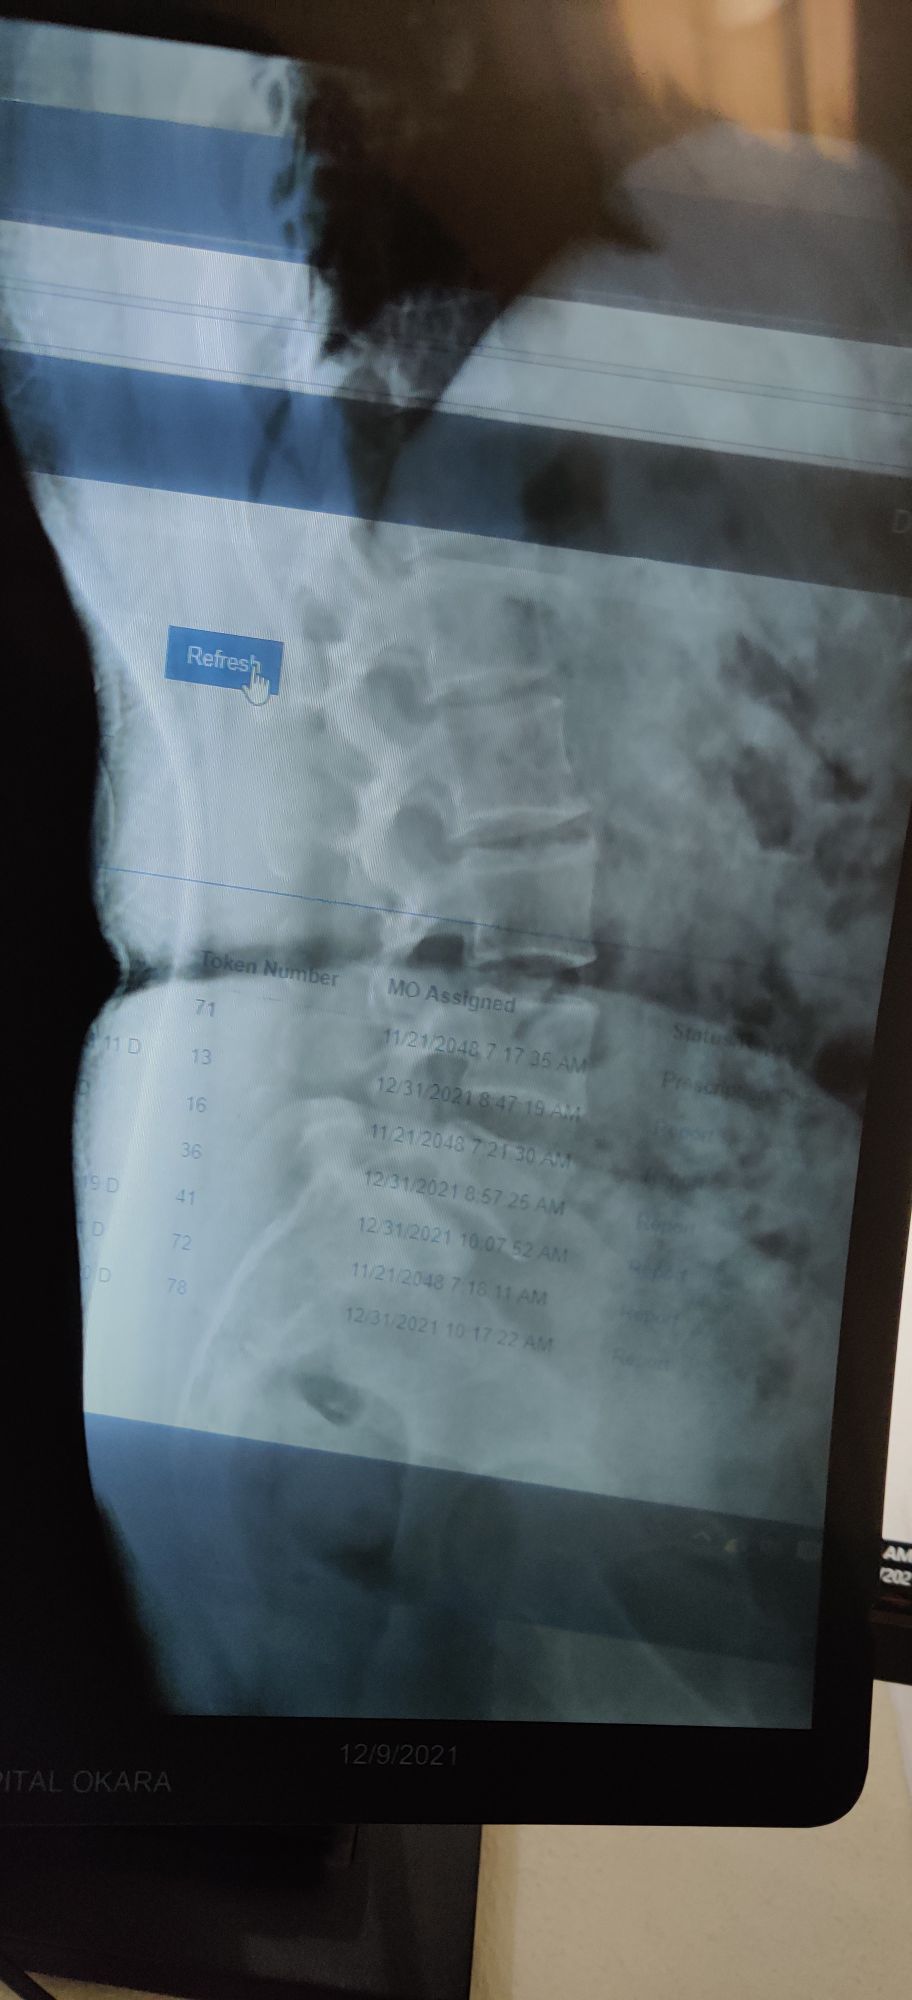

Lumbosacral spondylosis with spondylolisthesis

Xray

Spine

Ortho